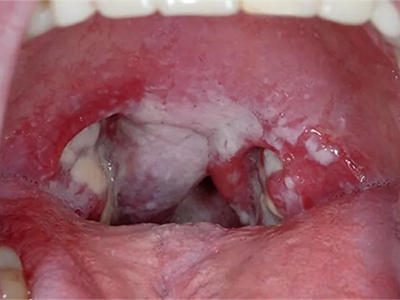

咽喉

白斑

鹅口疮咽喉处黏膜有白色斑块图

鹅口疮患者口腔黏膜产生白色斑块,甚至可以波及扁桃体、咽喉处,出现大片白斑,周围无明显的红、肿、热、痛等炎症反应,具有自愈性。